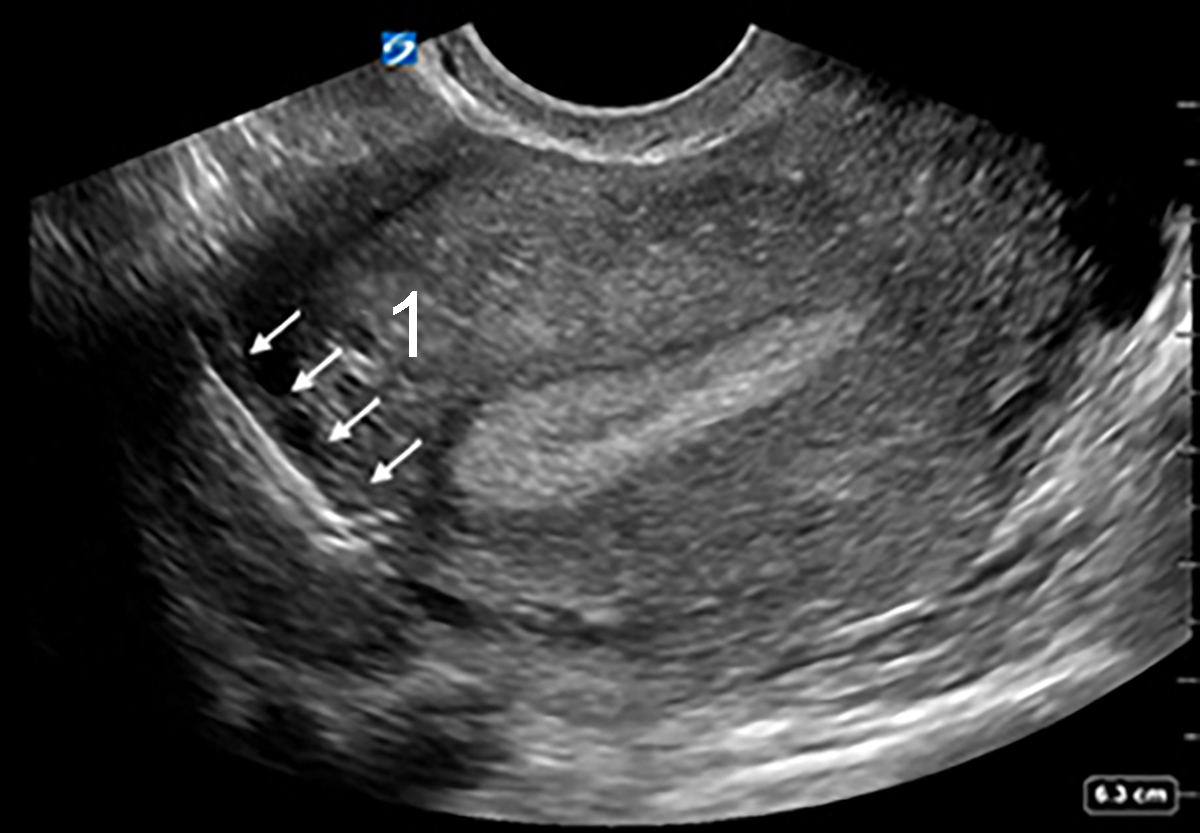

Bild: Transvaginaler (TV) Ultraschall des Beckens und Uterus mit disloziertem Intrauterinpessar (IUP), sagittal

1. IUP